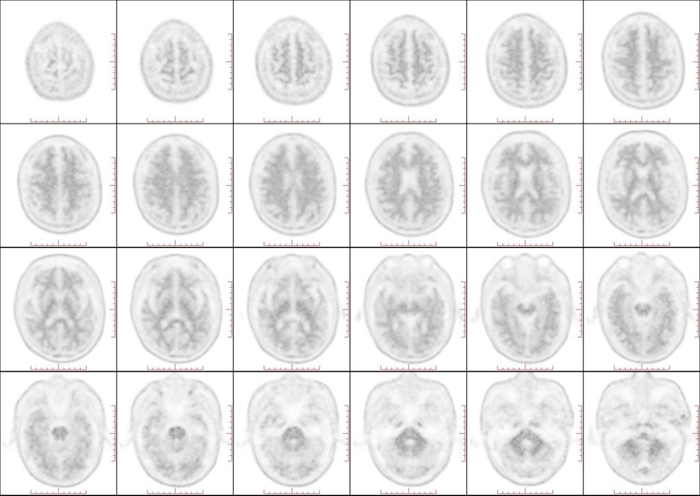

近日,一项旨在攻克阿尔茨海默病(AD)诊断难题的尖端技术在北京天坛医院成功落地。北京天坛医院核医学科与神经内科紧密协作,成功为一名记忆力下降患者完成了淀粉样蛋白(Aβ)PET显像剂氟[18F]贝他苯注射液的检查。此项检查标志着医院在阿尔茨海默病的早期、精准、无创诊断方面迈出了关键一步。

脑内Aβ蛋白异常沉积是AD病理的核心始发事件,可在症状出现前15-20年被探测到,从而抓住疾病干预的“黄金期”,实现早诊早治。Aβ PET是一种新型的脑显像技术,因其可以显示Aβ在脑中的分布和量化沉积斑块的严重程度,在AD精准诊断中具有重要价值。Aβ PET检测用于AD诊断,获得《2024美国阿尔茨海默病学会(AA)诊断和分期标准修订版》、《2024 国际工作组(IWG)推荐:阿尔茨海默病临床-生物学架构》、《2018中国痴呆与认知障碍诊治指南》等权威指南一致推荐。

随着Aβ-PET显像剂进入临床应用,以及AD治疗已经迈入靶向Aβ单抗精准治疗的新阶段,大量患者迫切需要通过Aβ PET显像进行疾病确诊及后期疗效评估。氟[18F]贝他苯注射液是国内首个获批的Aβ PET显像剂,为实现国内AD的早期、精准、无创诊断,提供了有利“武器”。北京天坛医院核医学科发挥自身的专业优势,积极参与 Aβ PET 技术的临床研究和应用推广,以期在疾病早期,当患者症状尚不明显时,及时准确地做出诊断,为患者赢得宝贵的治疗时间。